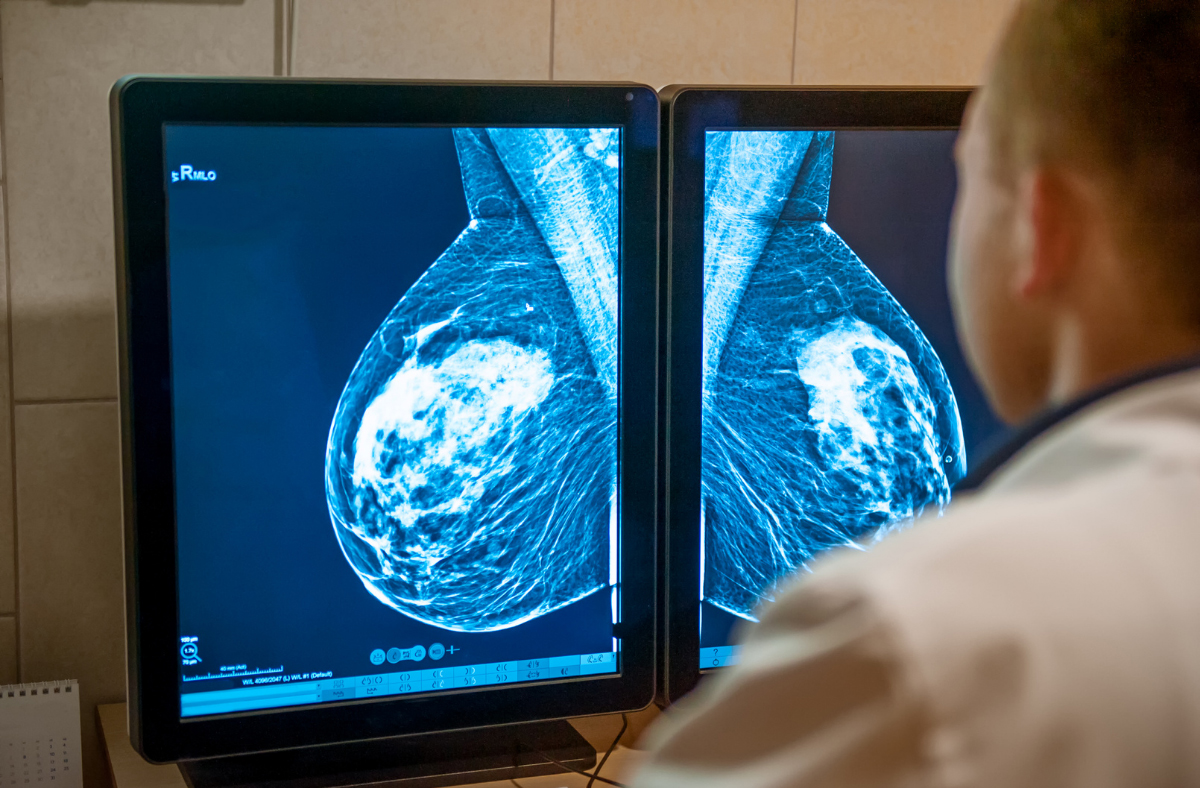

Cancer screenings, such as mammograms, colonoscopies, Pap smears, prostate specific antigen (PSA) tests and lung cancer screenings, were all put on pause for so many people through 2020 and even into 2021. These tests can detect cancer early and reduce people’s chances of dying from that cancer.

At the MemorialCare Todd Cancer Institute, we are dedicated to the early diagnosis, research, treatment and education of patients with cancer or serious blood disorders. We have advanced diagnostic screening tools that can make the screening experience less intimidating for patients. For example, we have a low-dose computed tomography (CT) scanner that can help detect cancer in individuals who are at high risk for lung cancer. The low-dose CT scanner can reduce mortality in these patients by as much as 20%. A benefit to low-dose radiation imaging is that the amount of radiation a person would receive is significantly reduced as compared to that of a standard-dose diagnostic CT.